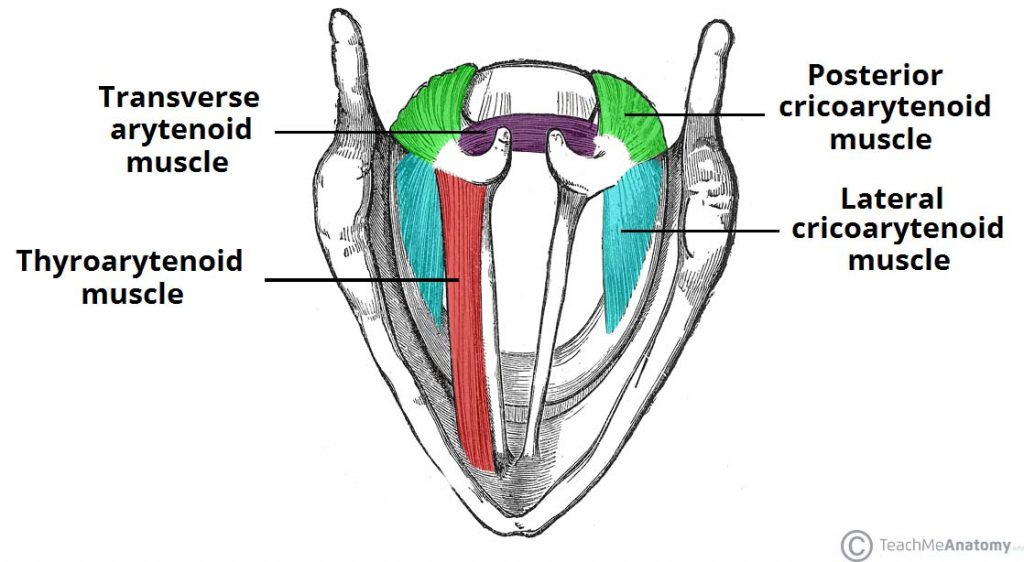

Muscle

關閉 Epiglotticus

- Thyroepiglotticus m

- Aryepiglotticus

Vocal fold

Motor: Recurrent laryngeal n.

- Arytenoid m.

- Transverse fiber / Oblique fiber

- Vocal fold adduction

- Post. cricoarytenoid

- Vocal fold abduction

- Lateral cricoarytenoid m.

- Vocal fold adduction

- Thyroarytenoid m.

- Arytenoid cartilage 往前

Motor: External laryngeal n.

- Cricothyroid m.